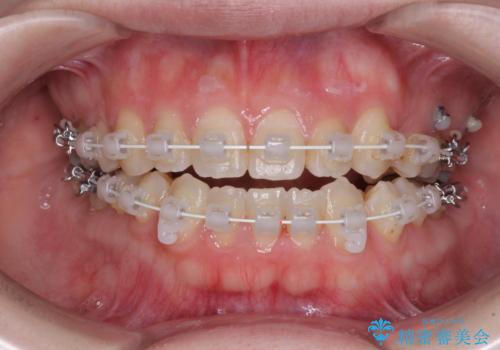

- 矯正装置

- 審美装置

- 左上の八重歯と前歯のデコボコを気にして来院された患者様です。

下顎が左側にズレており、下顎前歯は1歯欠損していたため、左上小臼歯1本を抜歯し、ワイヤー装置にて矯正治療を行うこととしました。

骨格のズレと歯の欠損があったため、仕上がりの調整に時間がかかると思いましたが、舌突出癖の改善や顎間ゴムの装着をしっかりと行ってくださったので、速やかに治療を終えることができました。